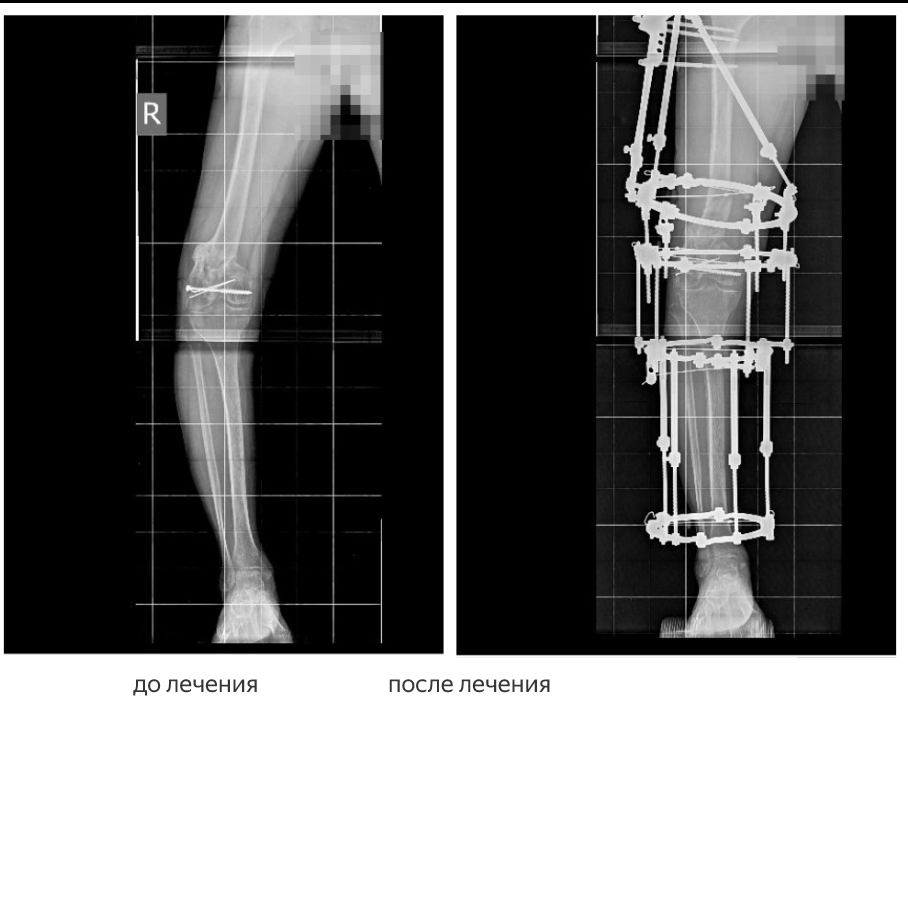

Второй житель ДНР получил тяжелую травму правого бедра в результате ДТП в марте 2024 года. Первоначальное лечение с применением комбинированного остеосинтеза не дало нужного результата — перелом сросся неправильно, сформировалась варусная деформация.

В НМИЦ ТО им. Г. А. Илизарова пациенту провели остеосинтез бедра аппаратом Илизарова и одномоментно скорректировали деформацию. В ходе лечения удалось добиться полной консолидации отломков в правильном положении. После снятия аппарата мужчина вернулся домой — его нога вновь стала полноценной опорой.

Оба случая — пример успешного применения метода чрескостного остеосинтеза по Илизарову, позволяющего исправлять даже самые сложные посттравматические деформации, которые не удалось вылечить традиционными способами.